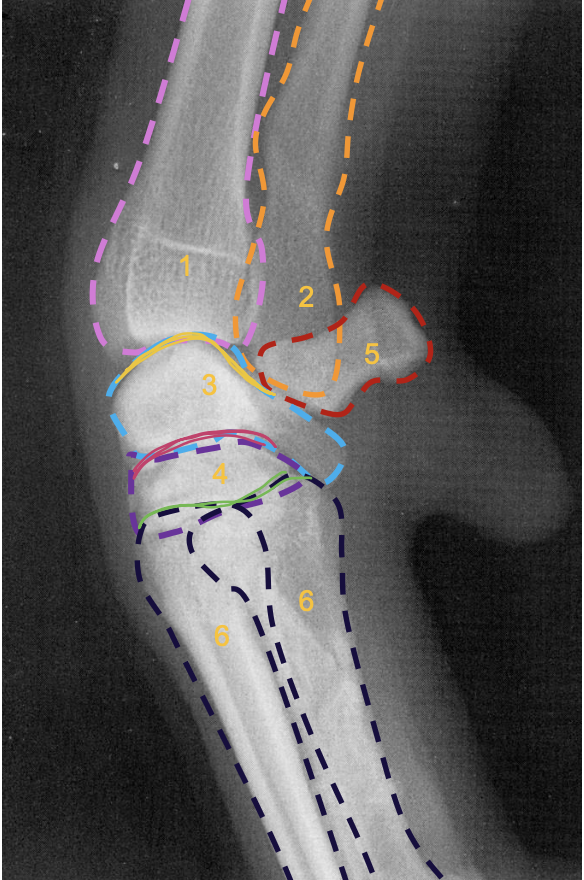

what is the pink line?

medial epicondyle of the humerus (makes 90 degree angle)

what is the purple line?

lateral condyle of humerus

what is the light blue line?

medial condyle of humerus

what is the green line?

medial coronoid process of the ulna

what is 1?

condyles of humerus

what is 2?

epicondyles of humerus

what is the red X marking?

anconeal process of the ulna